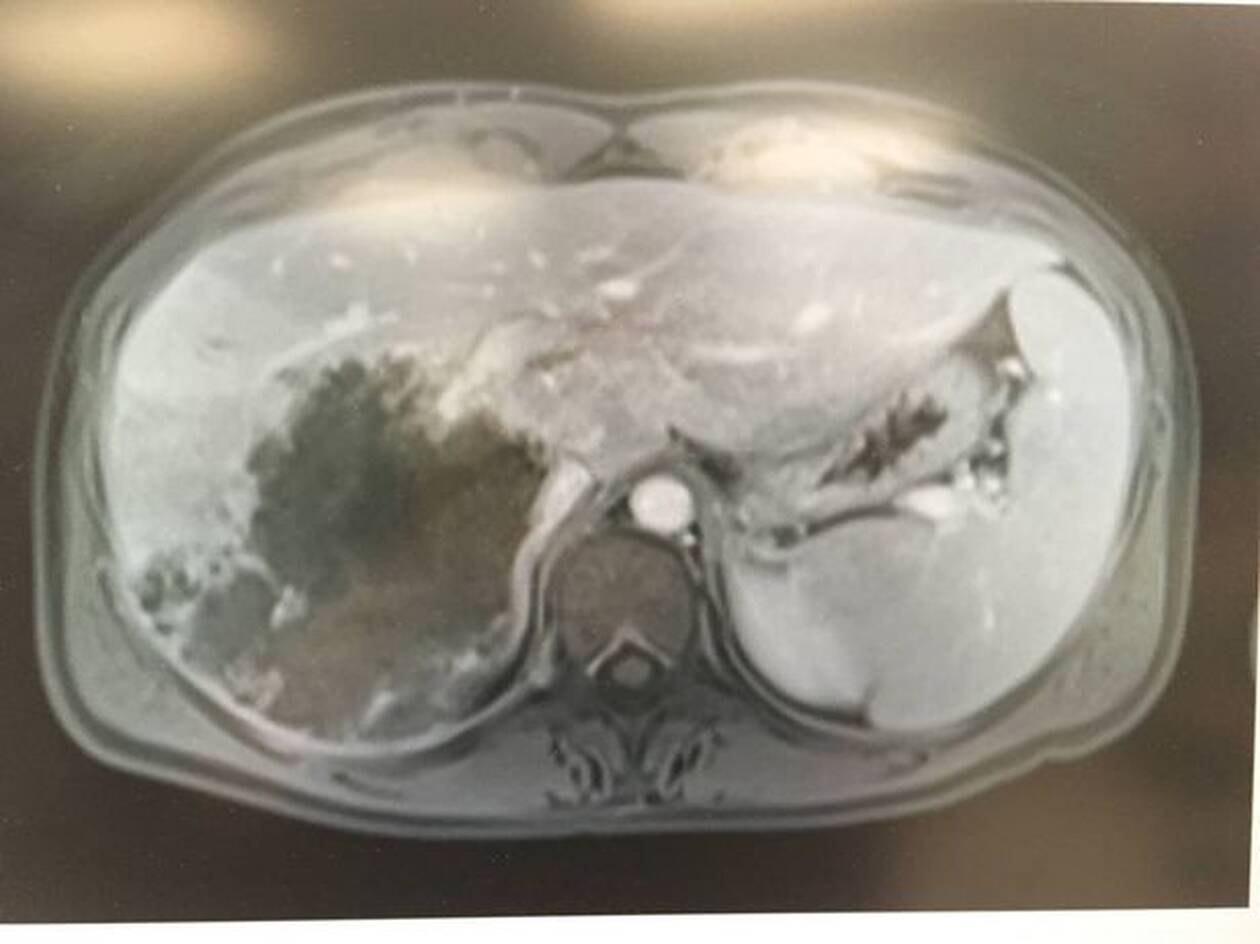

Τότε οι γιατροί εντόπισαν μια σκιά και αμέσως την ενημέρωσαν πως επρόκειτο για καρκίνωμα και μάλιστα σπάνιας μορφής, ο οποίος εμφανίζεται σε άτομα κάτω των 40 ετών.

Λίγο πριν ξεκινήσουν οι χημειοθεραπείες, έκανε συμπληρωματικές εξετάσεις που αποκάλυψαν τη φρικτή, αλλά όχι θανατηφόρα ασθένεια.

Η 36χρονη γυναίκα ζούσε μ’ ένα σκουλήκι στο συκώτι της

Η Cassidy ενημερώθηκε πως είχε προσβληθεί από ένα σκουλήκι-ταινία και όταν ρώτησε τους γιατρούς αν είναι καλά τα νέα, της απάντησαν πως είναι καλύτερα από αυτό που είχαν διαγνώσει αρχικά.

Το σκουλήκι ζούσε για σχεδόν 15 χρόνια στο συκώτι της, ενώ το κόλλησε από ζώο, το οποίο είχε φάει κάποιο τρωκτικό.